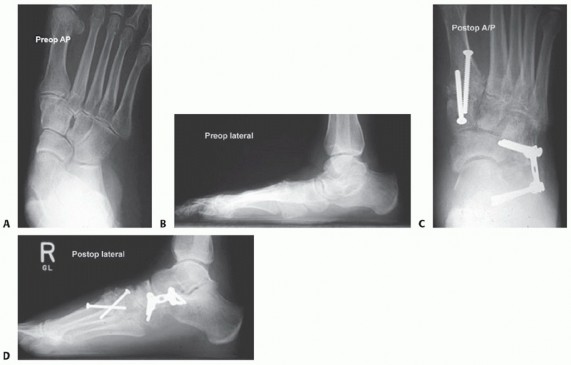

- TECH FIG 4 • Preoperative AP (A) and lateral (B) radiographs. Postoperative AP (C) and lateral (D) radiographs after lateral column lengthening through the calcaneocuboid joint. (Courtesy of Bruce Sangeorzan, MD.)

Secure the arthrodesis with a small H-plate, cervical plate, or semitubular plate (TECH FIG 4). Avoid overcompression and shortening of the lateral column.